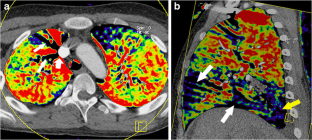

Fig. 3